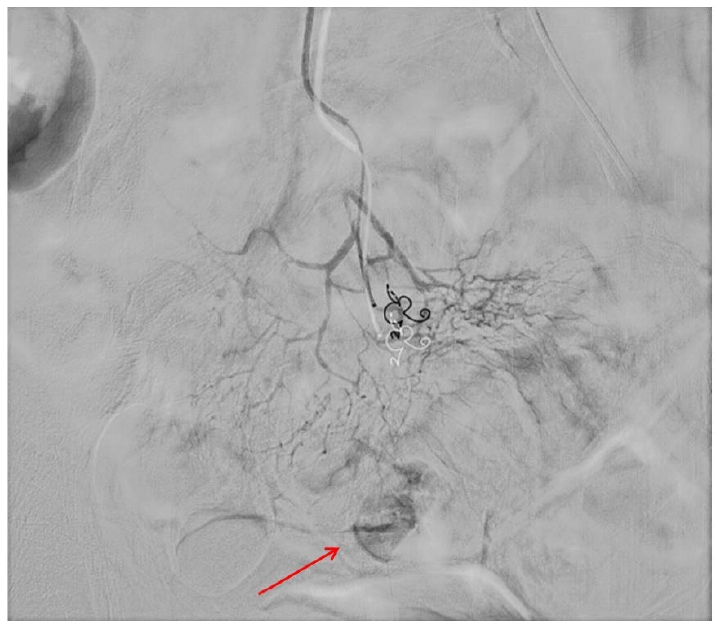

수술 중 병변의 위치를 찾기 위하여 병변으로 의심되는 부위에 클립을 결찰한 후 코일과의 상대적인 위치를 C-arm을 통해 확인하여 보정하는 과정을 거쳤다. 회결장동맥(ileocolic vessel)을 결찰한 뒤 장간막동맥(mesenteric branch)에 위치한 코일이 확인되었고(Fig. 4) C-arm을 통해 코일의 위치를 재확인하여 병변의 위치를 특정하였다. 리가슈어(LigaSureTM; Medtronic, Minneapolis, MN, USA)로 장간막을 나눈 후 장간막 반대편 경계를 따라 말단 회장 근처의 소장 절제술을 시행하였다(Fig. 5A). 절제된 소장 부위에서 궤양성 병변이 확인되어 소장을 봉합한 후 수술을 마무리하였다.

Figure 4.

Fluoroscopic location of the embolization coil. A radiograph of the pathologic specimen showed the presence of the microcoil within the ileal arterial branch.